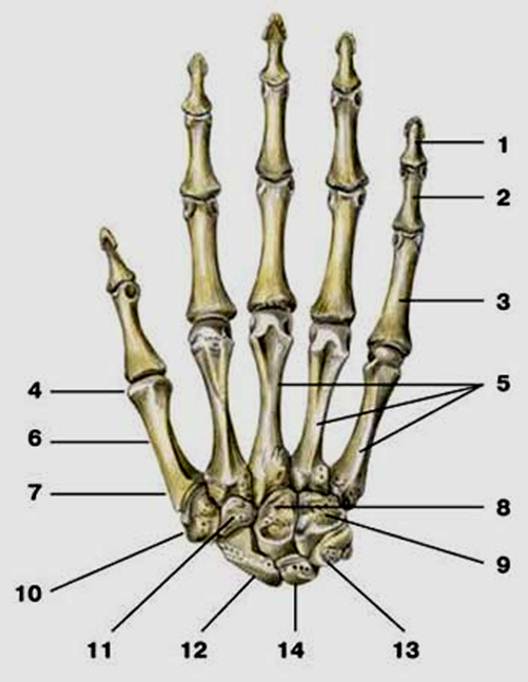

S: Числом 10 обозначена os trapezium (латинский язык).

S: Цифра 5 обозначает ossa metacarpi (латинский язык).

S: Цифрой 8 обозначена os capitatum

S: Числом 12 обозначена os scaphoideum

S: Числом 13 обозначена os triquetrum

S: Цифра 3 указывает на phalanx proximalis

S: Цифра 2 указывает на phalanx media

S: Цифра 1 указывает на phalanx distalis